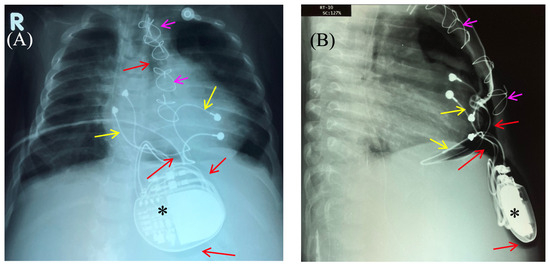

Fluoroscopy and chest and abdominal radiography revealed no signs of pneumothorax. A demarcated area of free air was visualized in the upper anterior abdominal wall along the midline, projecting to the pacemaker pocket. The passage of radiocontrast agent through the gastrointestinal tract was observed dynamically and found to be normal. No signs of hollow organ perforation or intestinal obstruction were detected (Figure 2, Figure 3 and Figure 4).

Figure 3. Control of the passage of radiocontrast agent (yellow arrow) through the gastrointestinal tract to exclude perforation of a hollow organ of the abdominal cavity. Frontal (A,C) and lateral (B) view of the chest X-ray 1 h (A,B) and 2.5 h (C) after radiocontrast agent administration. R: right side; L: left side.